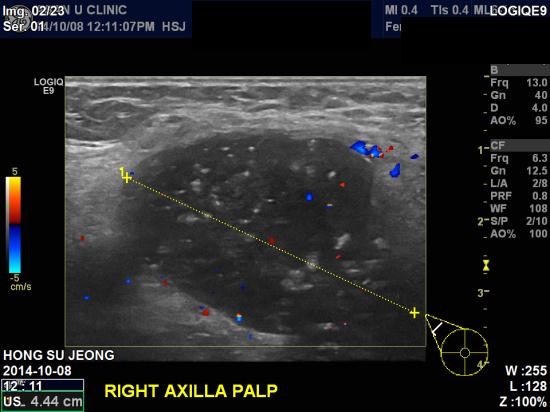

2달전 부터 우측 겨드랑이에 만져지는 멍우리 및

통증이 있어 내원하신 52세 여성분 입니다.

촉진시 우측 겨드랑이에 만져지는 혹이

있었고,

본원 초음파 검사상 우측 겨드랑이 림프절 비대 소견 및

우측 유방 12시 방향에 1.03cm 결절 소견 있어

조직검사

시행하였습니다.

조직검사 결과 상 우측 침윤성 유관암 및 겨드랑이 전이로 진단 되었습니다.